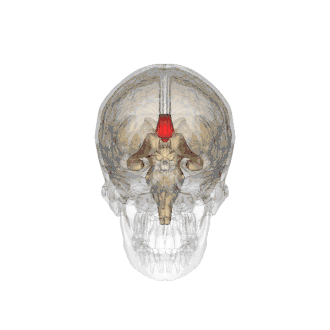

Le corps calleux (ou corpus callosum) est une commissure (moyen d'union entre deux parties) transversale du cerveau présente chez les mammifères placentaires[1]. C’est un faisceau d'axones (fibre nerveuse qui correspond au prolongement long, mince et cylindrique du corps cellulaire d'un neurone) interconnectant les deux hémisphères cérébraux. C'est la plus importante commissure du cerveau, car elle relie les huit lobes du cerveau entre eux (lobes frontaux, temporaux, pariétaux et occipitaux gauche et droit). Le corps calleux assure donc le transfert d'informations entre les deux hémisphères et ainsi leur coordination. Les autres commissures sont le fornix, le cingulum et la commissure blanche antérieure.

D’avant en arrière, on peut délimiter trois structures :

- le « genou » et le tiers antérieur du corps calleux (bec ou rostrum) sont ainsi formés par les fibres qui unissent les deux cortex (lobes) frontaux ;

- le tiers moyen (ou tronc) est formé par les fibres qui unissent les cortex pariétaux et temporaux ;

- la partie la plus postérieure, (bourrelet ou splenium), est formé par les fibres qui unissent les deux cortex occipitaux.